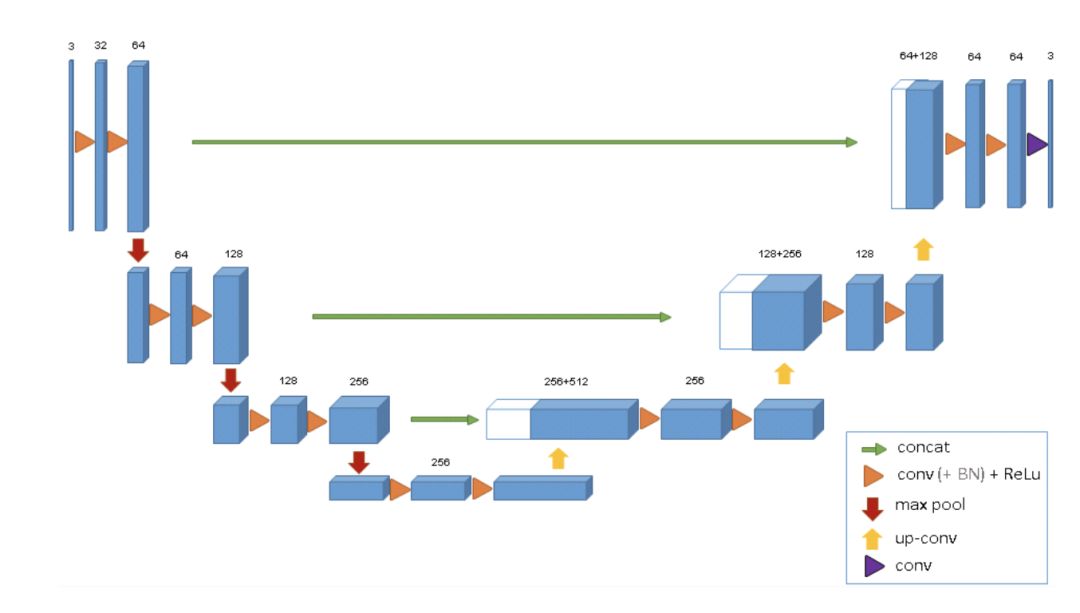

具体的网络结构就是将U-Net改为3D的形式。